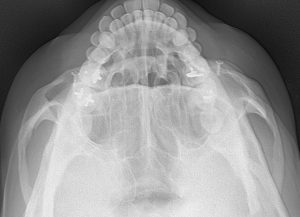

The cheekbones can be reduced by moving the zygoma and the zygomatic arch inward, as a combined unit, through osteotomies or bone cuts. From inside the mouth an oblique straight line or L-shaped osteotomy is done through the main body of the zygoma and from a small temporal incision the attachment of the tail of the zygomatic arch is cut. This allows a cheekbone reduction to be done by moving these bone segments inward and fixing them in a more narrowed position with small plates and screws. These types of osteotomies are the primary method of cheekbone reduction surgery and produce the greatest amount of facial narrowing.

Cheekbone reduction osteotomies narrow the side of the face by moving the entire zygomatic arch inward. This operation is about changing the projection (peak of the convexity) of the zygomatic arch by moving its two ‘ends’ inward. How effective this would be for any patient with a wider face or large ‘cheekbones’ requires a preoperative x-ray to look at the natural convexity of their arches to determine how much contribution of the width comes from the zygomatic arches.